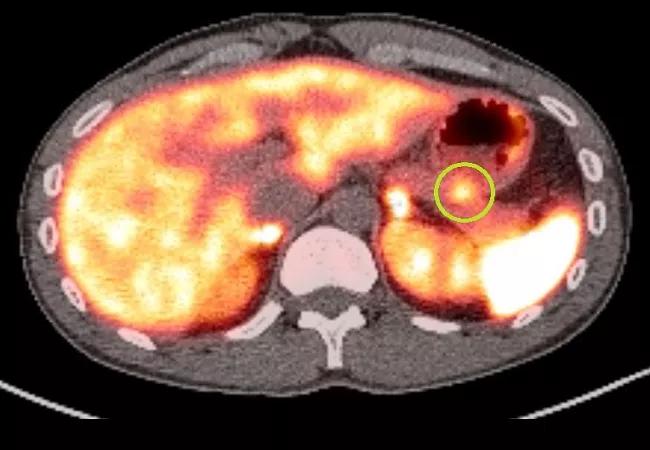

PET scan image of lesion.

A gallium-68 dotatate PET scan of the pancreatic lesion shows prominent dotatate uptake (green circle).

A CT of the patient’s chest, abdomen and pelvis showed a focal arterially-enhancing 11 mm x 10 mm lesion in the tail of the pancreas, which became iso-enhancing on the portal venous phase. The differential diagnosis was a pancreatic non-islet cell tumour. The diagnosis was further supported by prominent dotatate uptake (SUVmax 9.4) of the same lesion on a gallium-68 dotatate PET scan.